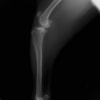

術前左後肢側面像

術前のTPAは左後肢33.1°右後肢26.8°でしたがTPLO実施により左後肢5.5°右後肢12°に矯正されました。